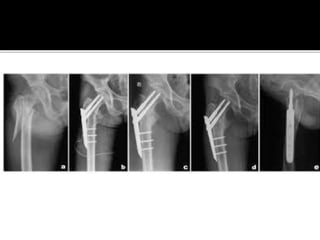

Failed

Subtrochanteric

fracture fixation

with broken DCS

and plate

After 51 days